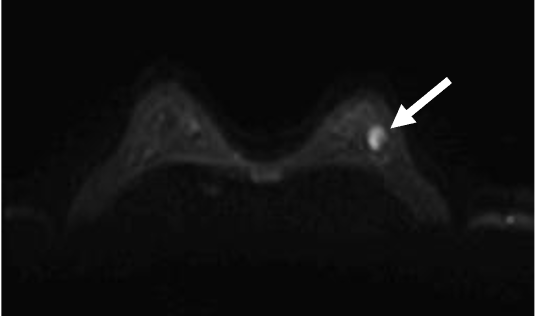

検診で指摘された左乳房腫瘤に対してMRI精査を行った症例である。BPEはminimalで病変の同定は容易であった。拡散強調像では明瞭な高信号あり、ADCの低下を認め、細胞密度は高いと考えられた。造影MRIにて辺縁不整な形状である事が明瞭となり、ダイナミック早期相では辺縁優位に造影効果を認め、TIC( Time intensity curve)ではFast-plateauパターンを示し乳癌を疑った。

cT1cN0M0の診断となり乳房温存術、術後放射線療法が施行された。

病理では硬性型の浸潤性乳管癌と診断された。

当該疾患の診断における造影MRIの役割

病変の辺縁の性状、境界、内部の造影パターンの把握にダイナミック造影MRIが必須である。今回の症例は単発病変であったが、多発病変でBPE(background parenchymal enhancement)がある症例では病変部と非病変部の区別に注意が必要である。